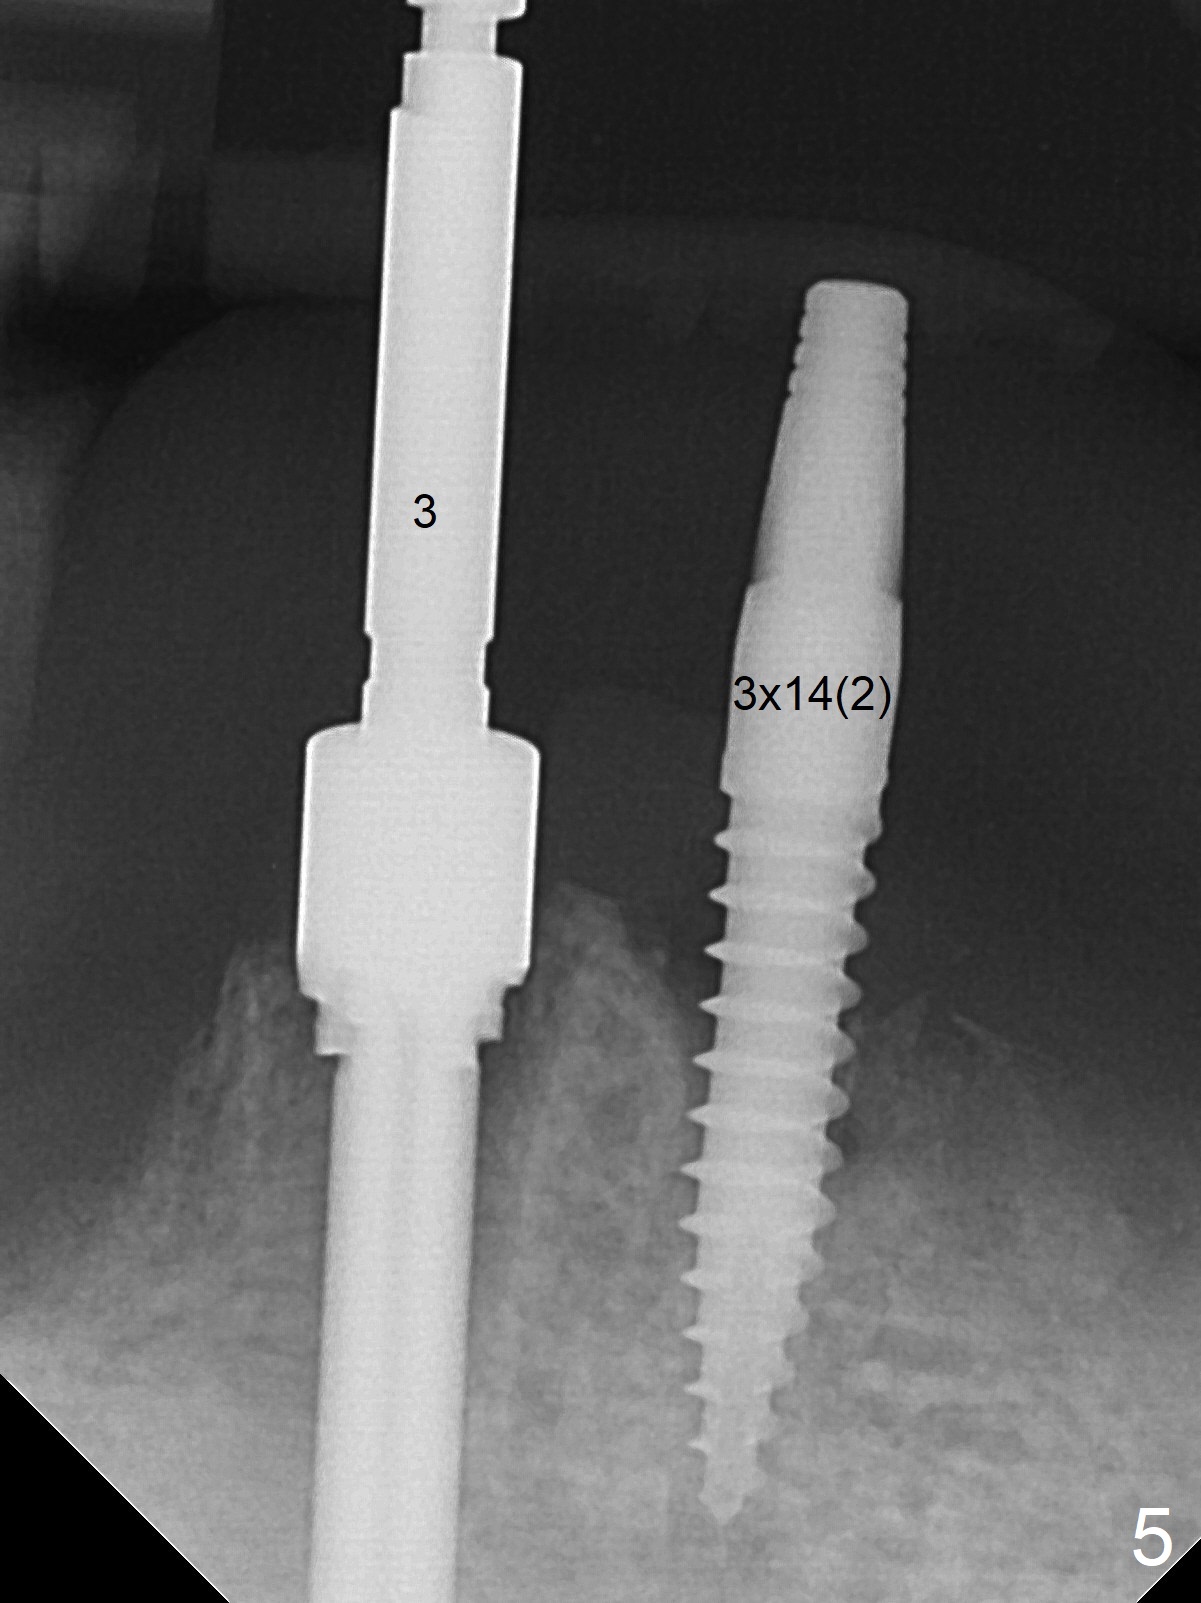

When the patient returns for #26 extraction and immediate implant and #27 RCT, it appears that the tooth #27 with subgingival margin distolingually is non-salvageable (Fig.1). She has dry mouth. Osteotomy is initiated in the lingual slope (Fig.4 red dashed line) of each socket with 1.2 and 2 mm drills for 16 and 19 mm at #26 and 27, respectively (Fig.2,3). The depth at #27 is subsequently reduced, while a 3x14(2) mm dummy implant is placed at #26 (Fig.5,6). A 3.8x13 mm implant is placed at #27 smoothly, while insertion of a 3x16(4) mm definitive implant (by mistake) has resistance (Fig.7). When the depth at #26 increases, there is feeling of perforation. The apex of the implant is truncated prior to reinsertion (Fig.8 >).